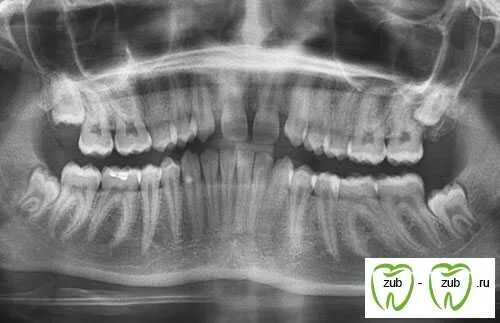

У ребенка нет зачатка постоянного зуба